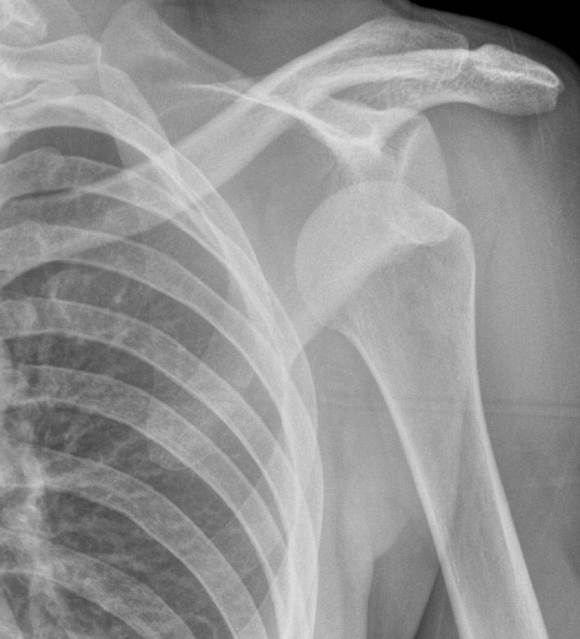

LUXACION ANTERIOR: